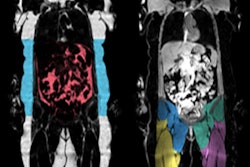

AMRA's technology translates images from a six-minute whole-body MRI scan into 3D-volumetric fat and muscle measurements that can then be used to evaluate a patient's body composition, according to the firm.